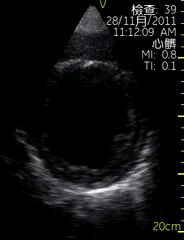

胸骨旁左室长轴切面

| 图像名称: | 胸骨旁左室长轴切面(二维) |

| 胸骨旁左室长轴切面(二维) |

| 胸骨旁左室长轴切面(二维) | | 介绍重点: | 长轴切面心肌收缩有力、二尖瓣前后叶呈镜向运动 |

| 室间隔回声中断,可见明显缺口,左室增大 |

| 左房、左室增大,室壁运动幅度降低;二尖瓣启闭受限; | | 临床用途: | 评估房室大小,心脏功能;(正常图像) |

| 室间隔缺损; |

| 左室收缩功能降低 |